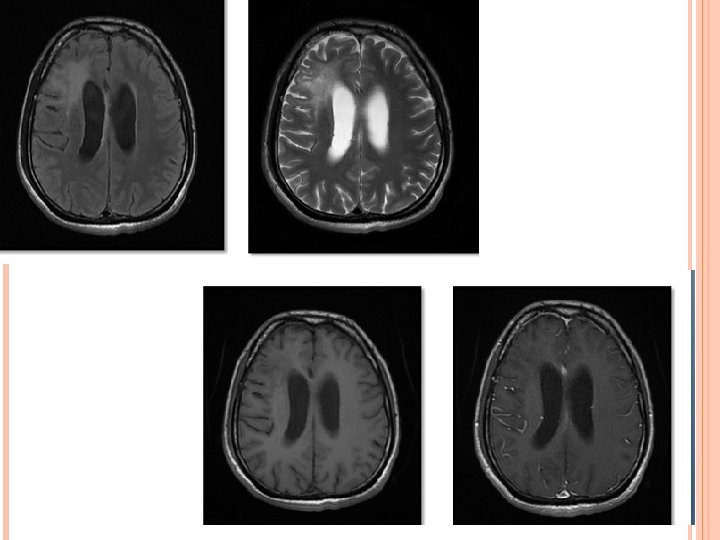

PRIMARY CNS LYMPHOMA • Usually Non-Hodgkin`s(B cell type) lymphoma • Location: Basal ganglia. Periventricular. Corpus callosum. • Presentation: Seizures, Headaches, Focal neurological deficit.

PRIMARY CNS LYMPHOMA IMAGING: CT-Typically a solitary hyperdense mass on NECT however multifocal in 50% cases. MR-Iso to hypointense on T 1 W and T 2 W image with diffusion restriction. Enhancement pattern are variable homogenous/heterogenous/ring like. Edema and mass effect in half of the lesion. Increase choline peak on MRS and increase Thallium uptake on SPECT.